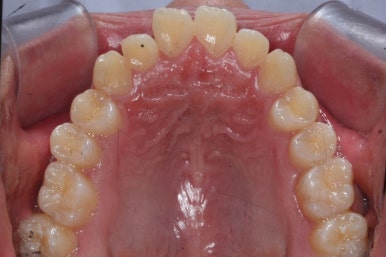

위 사진들은 부산주걱턱교정 키다리아저씨치과에 내원하셨을 당시의 입안 모습입니다.

입 안의 모습에서도 주걱턱의 특징으로는

하악이 앞으로 나와있습니다.

윗니는 뻐드러지고 아래 앞니는 뒤쪽으로 쓰러져 있습니다.

교합이 맞지 않습니다.